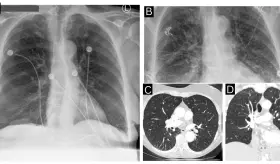

Este caso destaca la importancia de los estudios de imagen multimodales y plantea la necesidad de reconsiderar las estrategias de detección en mujeres no fumadoras, población en la que se observa un incremento creciente de esta neoplasia.

El cuadro se caracterizó por neumonía necrotizante, aleteo auricular con respuesta ventricular rápida, insuficiencia cardíaca biventricular y formación de trombos intracardíacos bilaterales.

Aunque inicialmente se sospechó una embolia pulmonar, los estudios descartaron tromboembolismo y evidenciaron una lesión quística mediastínica que, sin intervención quirúrgica, presentó una notable regresión posparto.